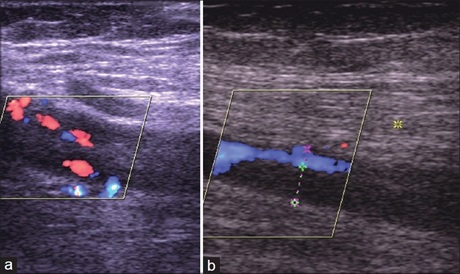

Utilization Pattern of Doppler Ultrasound Scan at the University of Benin Teaching Hospital

Dr. Igbinedion Blessing Ose‑Emenim, Ogbeide Osesogie Usuanle (Author)

15-19

Views | PDF/EPUB Downloads : 292 / 25 / 24

DOI: https://doi.org/10.82235/wajr.vol22no1.295